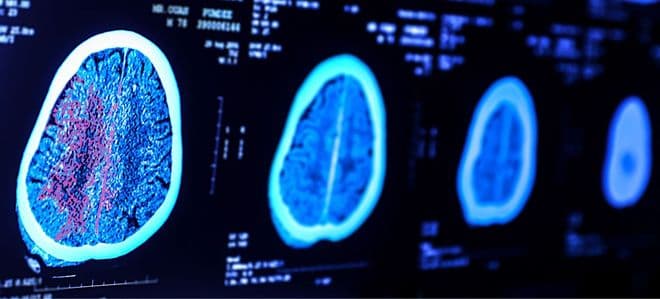

Maio Cinza alerta para câncer cerebral que tem alta taxa de mortalidade